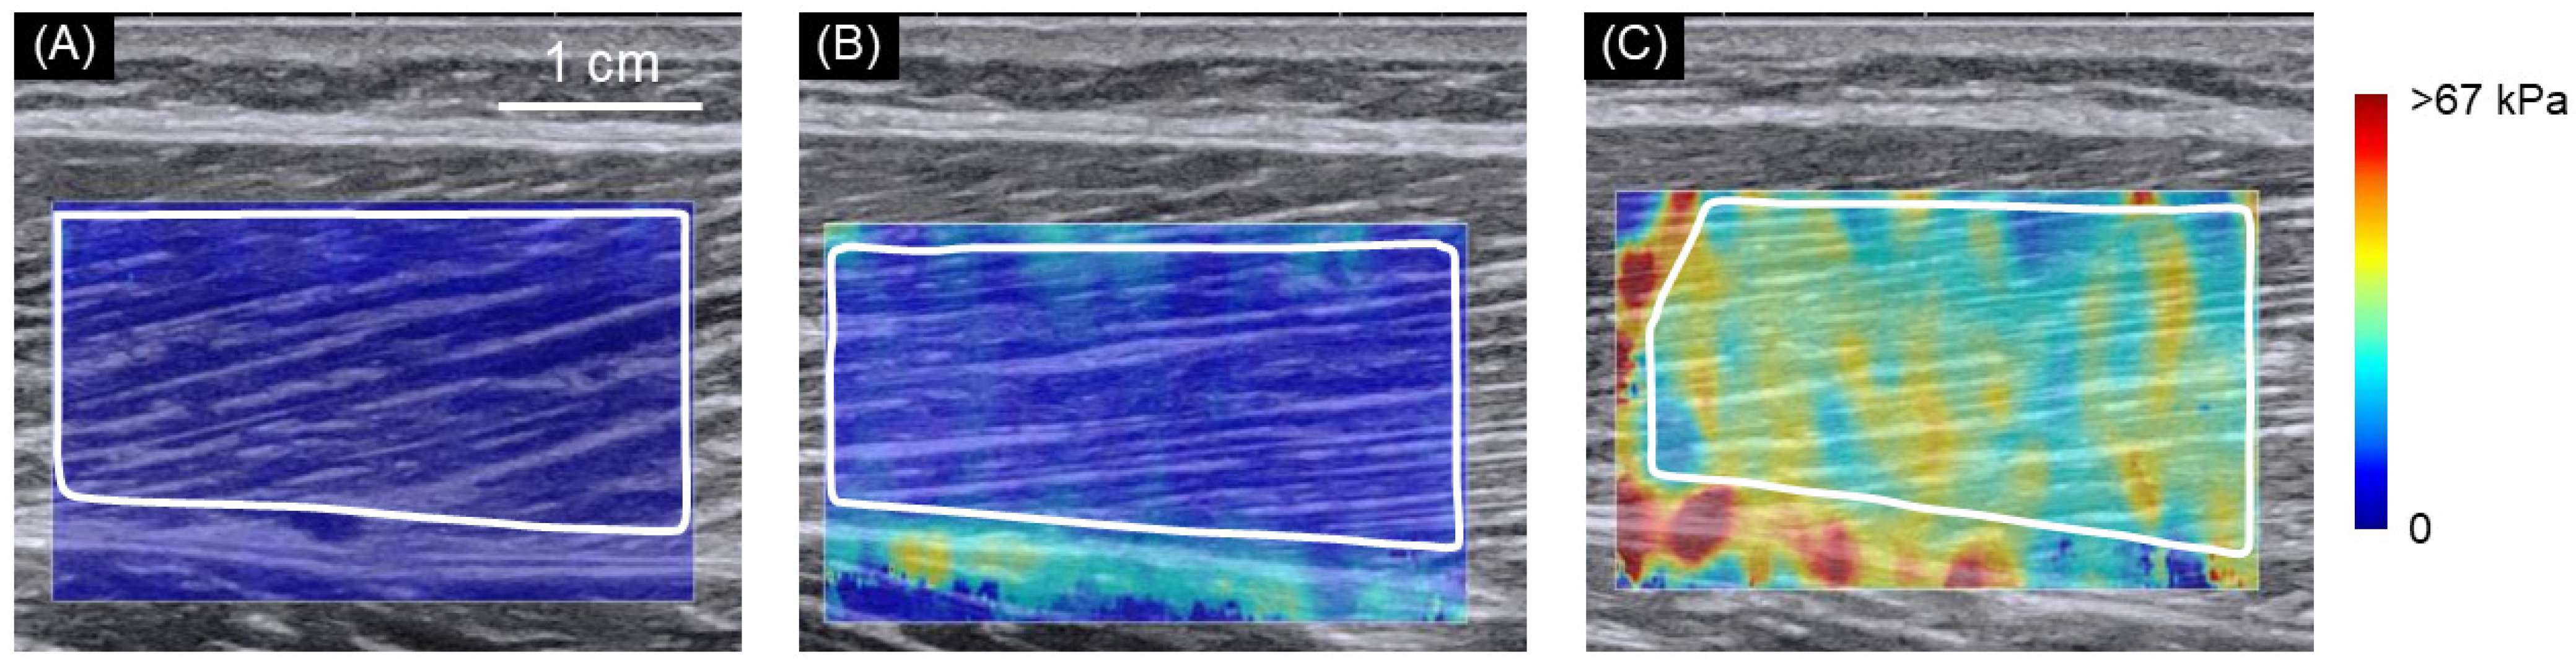

2.2. SWE Measurements